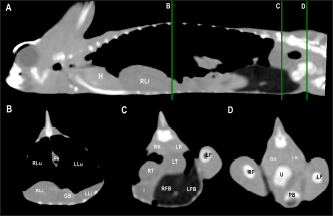

Fig. 5. Sagittal precontrast CT image displayed in soft tissue window (A) and selected corresponding transverse images represented as green line section, displayed in soft tissue (B, D–G) and lung window (C) at the level of the lungs, liver (D), gastrointestinal tract (E), fat bodies (F), and kidneys/urinary bladder (G) in a panther chameleon (F. pardalis). The right of the patient is on the left of the image. RLu, right lung; LLu, left lung; Es, esophagus; RLi, right liver lobe; LLi, left liver lobe; St, stomach; I, intestine; GB, gallbladder; RK, right kidney; LK, left kidney; RT, right testicle; LT, left testicle; Co, colon; RFB, right fat body; LFB, left fat body; U, urinary bladder with intraluminal content (urate salts) in the lumen visualized as multiple irregular mineral attenuating structures.

Lungs

Due to the air attenuation of both lung fields and air sacs, it was not possible to delineate well-defined limits between them in a soft tissue window, where they were visualized together as a large air-attenuating structure (Figs. 5 and 6). Air sacs occupy more than two-thirds of the dorsal coelom, and lung volume is wide variable depending on their degree of expansion. Because of this, no measurements for lung size were taken. With the lung window, the lung parenchyma in the prehilar portion of the lungs appeared as a thin, faintly outlined, homogeneous, and hypoattenuating area surrounding an air-filled cavity (Fig. 5); in the posthilar portion of the lungs, the parenchyma was barely visible. A transverse septum could be observed as a thin, hyperattenuating structure along the lungs. The caudal portion of the gas-attenuating structure corresponded to the air sacs (Fig. 6).

The liver was observed as a structure with low soft tissue attenuating values and it was incompletely bilobed. The right lobe was larger than the left one (Figs. 5, 6, and 8). After contrast administration, the liver parenchyma showed homogeneous contrast enhancement. The hepatic veins and CVC were better defined from the adjacent parenchyma as a hyperattenuating tubular structure. The liver measurements are included in Table 1 and pre and postcontrast attenuation values are included in Table 2.

The gallbladder could be identified in the caudoventral border of the liver, between the two lobes, located in the ventral aspect of the medium coelom. It was slightly lateralized to the right side of the body and the intestinal loops and fat bodies were its caudal landmark. The gallbladder was observed in all veiled and panther chameleons as a fluid attenuating circular structure (Figs. 5 and 6) with no visible wall in precontrast images. In postcontrast images, the thin wall of the gallbladder enhanced homogeneously, and the content was hypoattenuating in comparison with the liver parenchyma (Fig. 7).

The intestines were found in the caudoventral coelomic cavity, between the liver cranially, the lungs craniodorsally, and the kidneys, gonads, and pelvis caudodorsally. The intestines were visualized in all animals. Intestinal loops were seen as tubular structures with a soft tissue attenuation wall and with intraluminal small gas bubbles (Figs. 5–7). However, the different intestinal segments could not be identified. Only the colon could be differentiated with gas or feces when it was distended (Fig. 5). Pre and postcontrast attenuation values can be consulted in Table 2.

The testicles could be visualized in all male veiled chameleons (7/7; 100%) and in 11 of 13 (84.6%) male panther chameleons. The testicles were located in the caudo-dorsal part of the coelom ventral to the lumbar region. They were delimited ventrally by the intestines and fat bodies, caudally by the kidneys, and cranially by the lungs and the stomach. The right testicle was cranial to the left one (Figs. 5 and 6). These gonads were circular bilateral almost symmetrical homogenous soft tissue attenuating structures, mildly hypodense in comparison to the kidneys on plain images. They show mild diffuse contrast enhancement.

Fat bodies

Kidneys

Urinary bladder